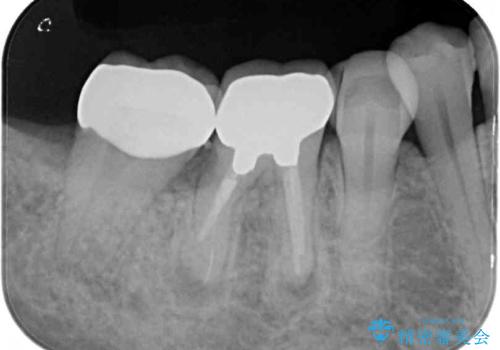

一番奥の歯は歯根の一部を残した状態で、手前の歯とブリッジが装着されていました。

奥歯は歯根周辺の歯槽骨が広範囲に失われており、抜歯が必要と判断されました。

ブリッジの手前側の歯は、根管治療が必要な状態でした。